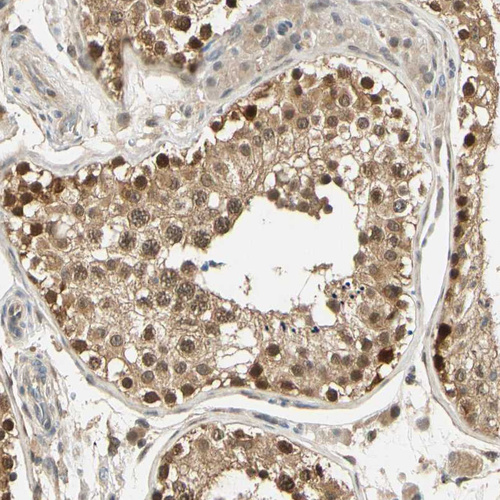

Immunohistochemical staining of human testis shows moderate to strong nuclear and cytoplasmic positivity in cells in seminiferous ducts.